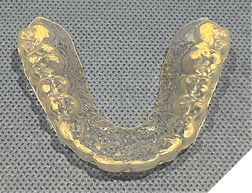

The majority of the orthodontic practices offer a period of “supervised retention” to their patients and communicates the customized retention recommendation with the patient’s general dentists. It is extremely important to work as a team to achieve long term clinical success in maintaining a functional bite and aesthetic smile. The general dentists continue to see their patients on a regular basis and have an opportunity to assess the orthodontic retainers and the bite after the supervised retention period is completed by the orthodontists. With great care, orthodontic retainers would serve for a long time (Fig. 1) without any major issues. However, in some cases, the failure to notice the clinical problems early on results in functional issues that would require a comprehensive orthodontic treatment to correct it (Fig. 2).

Fig. 1A

Fig. 1B

Fig. 1C